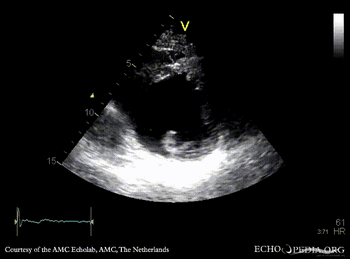

Infarction of posterior and inferior wall

PLAX: dilated left ventricle, akinesia of posterior wall PSAX: akinesia of posterior and inferior wall